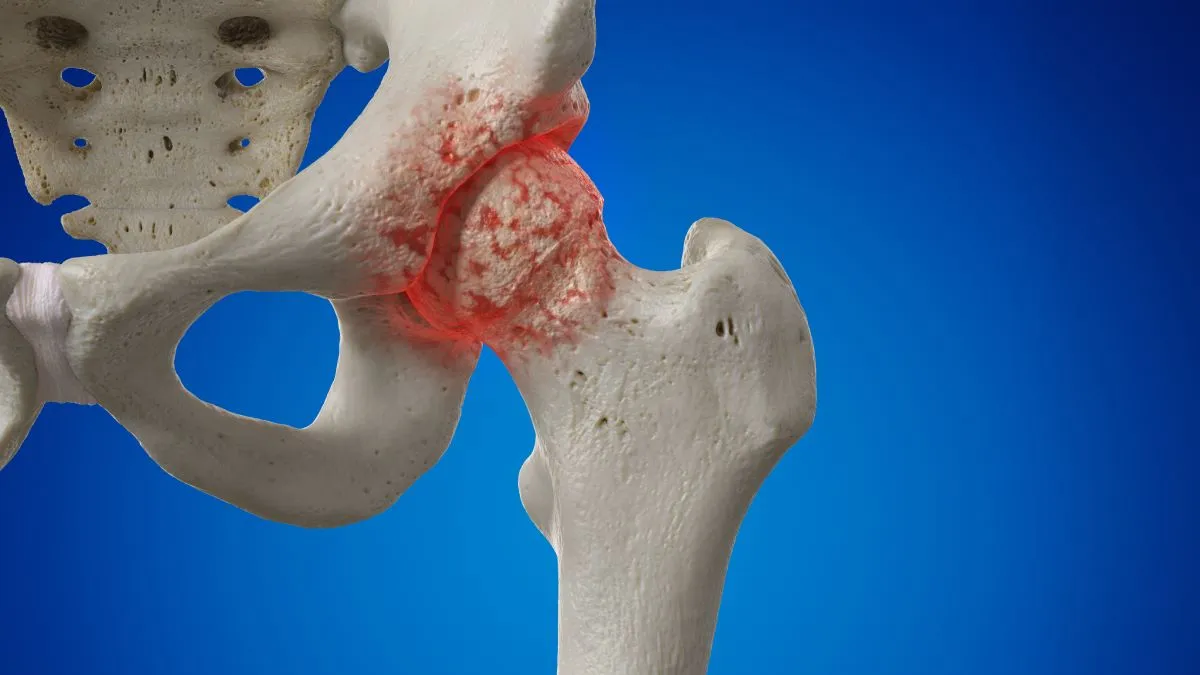

대표적인 고관절 질환 중 하나는 '대퇴골두 무혈성 괴사'입니다. 이는 허벅지 뼈 윗부분에 위치한 대퇴골두로 가는 혈류가 차단되어 그 부위의 뼈 조직이 죽는 상태를 말합니다. 괴사된 대퇴골두에 지속적인 압력이 가해지면 해당 부위가 골절되어 주변 고관절에도 심각한 손상을 줄 수 있습니다.